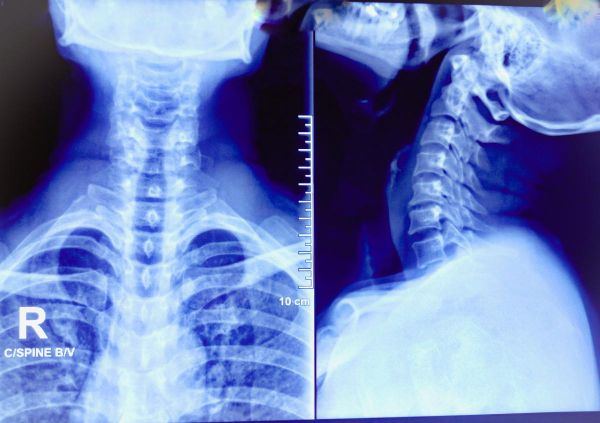

颈椎问题:长时间低头看手机或电脑屏幕可能导致颈椎问题,如颈椎疼痛和僵硬。这种姿势会增加颈部肌肉和椎间盘的压力,长期下去可能导致椎间盘损伤和颈部疼痛。腰椎问题:久坐时,腰部不正确的姿势可能导致腰椎问题,如腰椎间盘突出和腰椎疼痛。不稳定的躺椎和长期的压力可能损伤腰部肌肉和韧带。

坐骨神经痛:长时间坐姿不正可能增加坐骨神经受压的风险,导致坐骨神经痛。这种疼痛通常从腰部向下延伸,影响臀部、大腿和小腿。肩膀和背部问题:不正确的坐姿也可能导致肩膀和背部的问题,如肩部疼痛和背部疼痛。这可能是由于长时间的驼背姿势或不正确的椅子和桌子高度引起的。